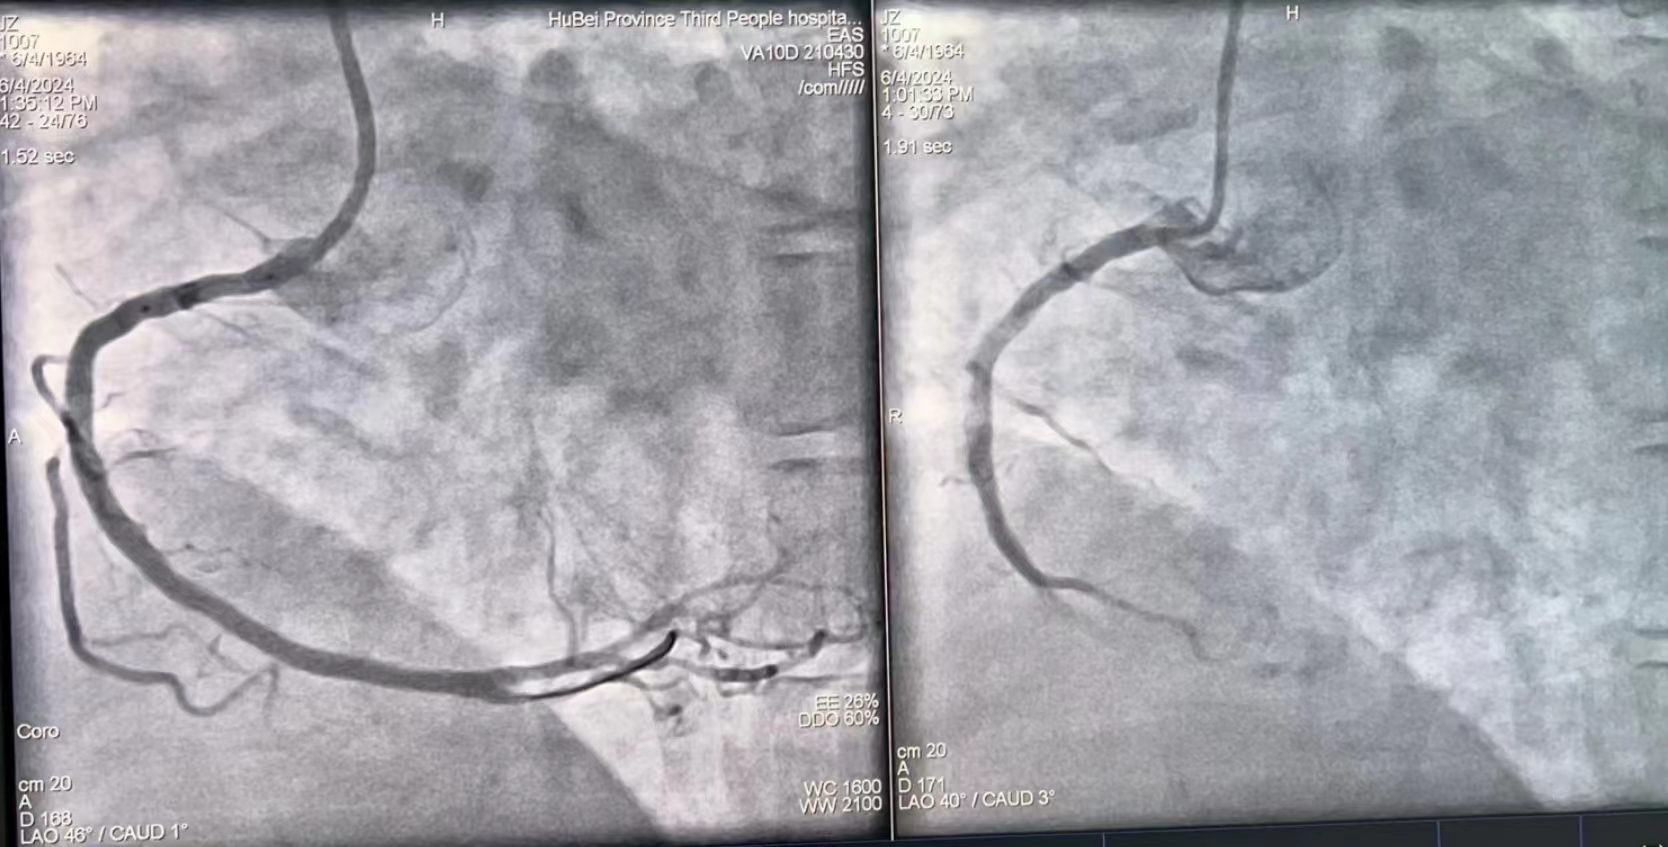

术后(左)与术前(右)对比

6月5日上午,夏爹爹外出购物,因天气炎热且购买物品太多,热得满头大汗、口干舌燥。到家后,他马上从冰箱中拿出一大瓶冷饮一饮而尽,酣畅淋漓之后,夏爹爹突感胸闷难耐,家人见状顿感不妙,急忙呼叫120送至91porn (湖北省中山91porn ),行心电图检查后考虑急性心梗,心血管内科介入团队迅速启动,经胸痛绿色通道将夏爹爹直送导管室手术,半小时不到就开通了导致夏爹爹犯病的“犯罪”血管,把夏爹爹从死亡线上拉了回来。